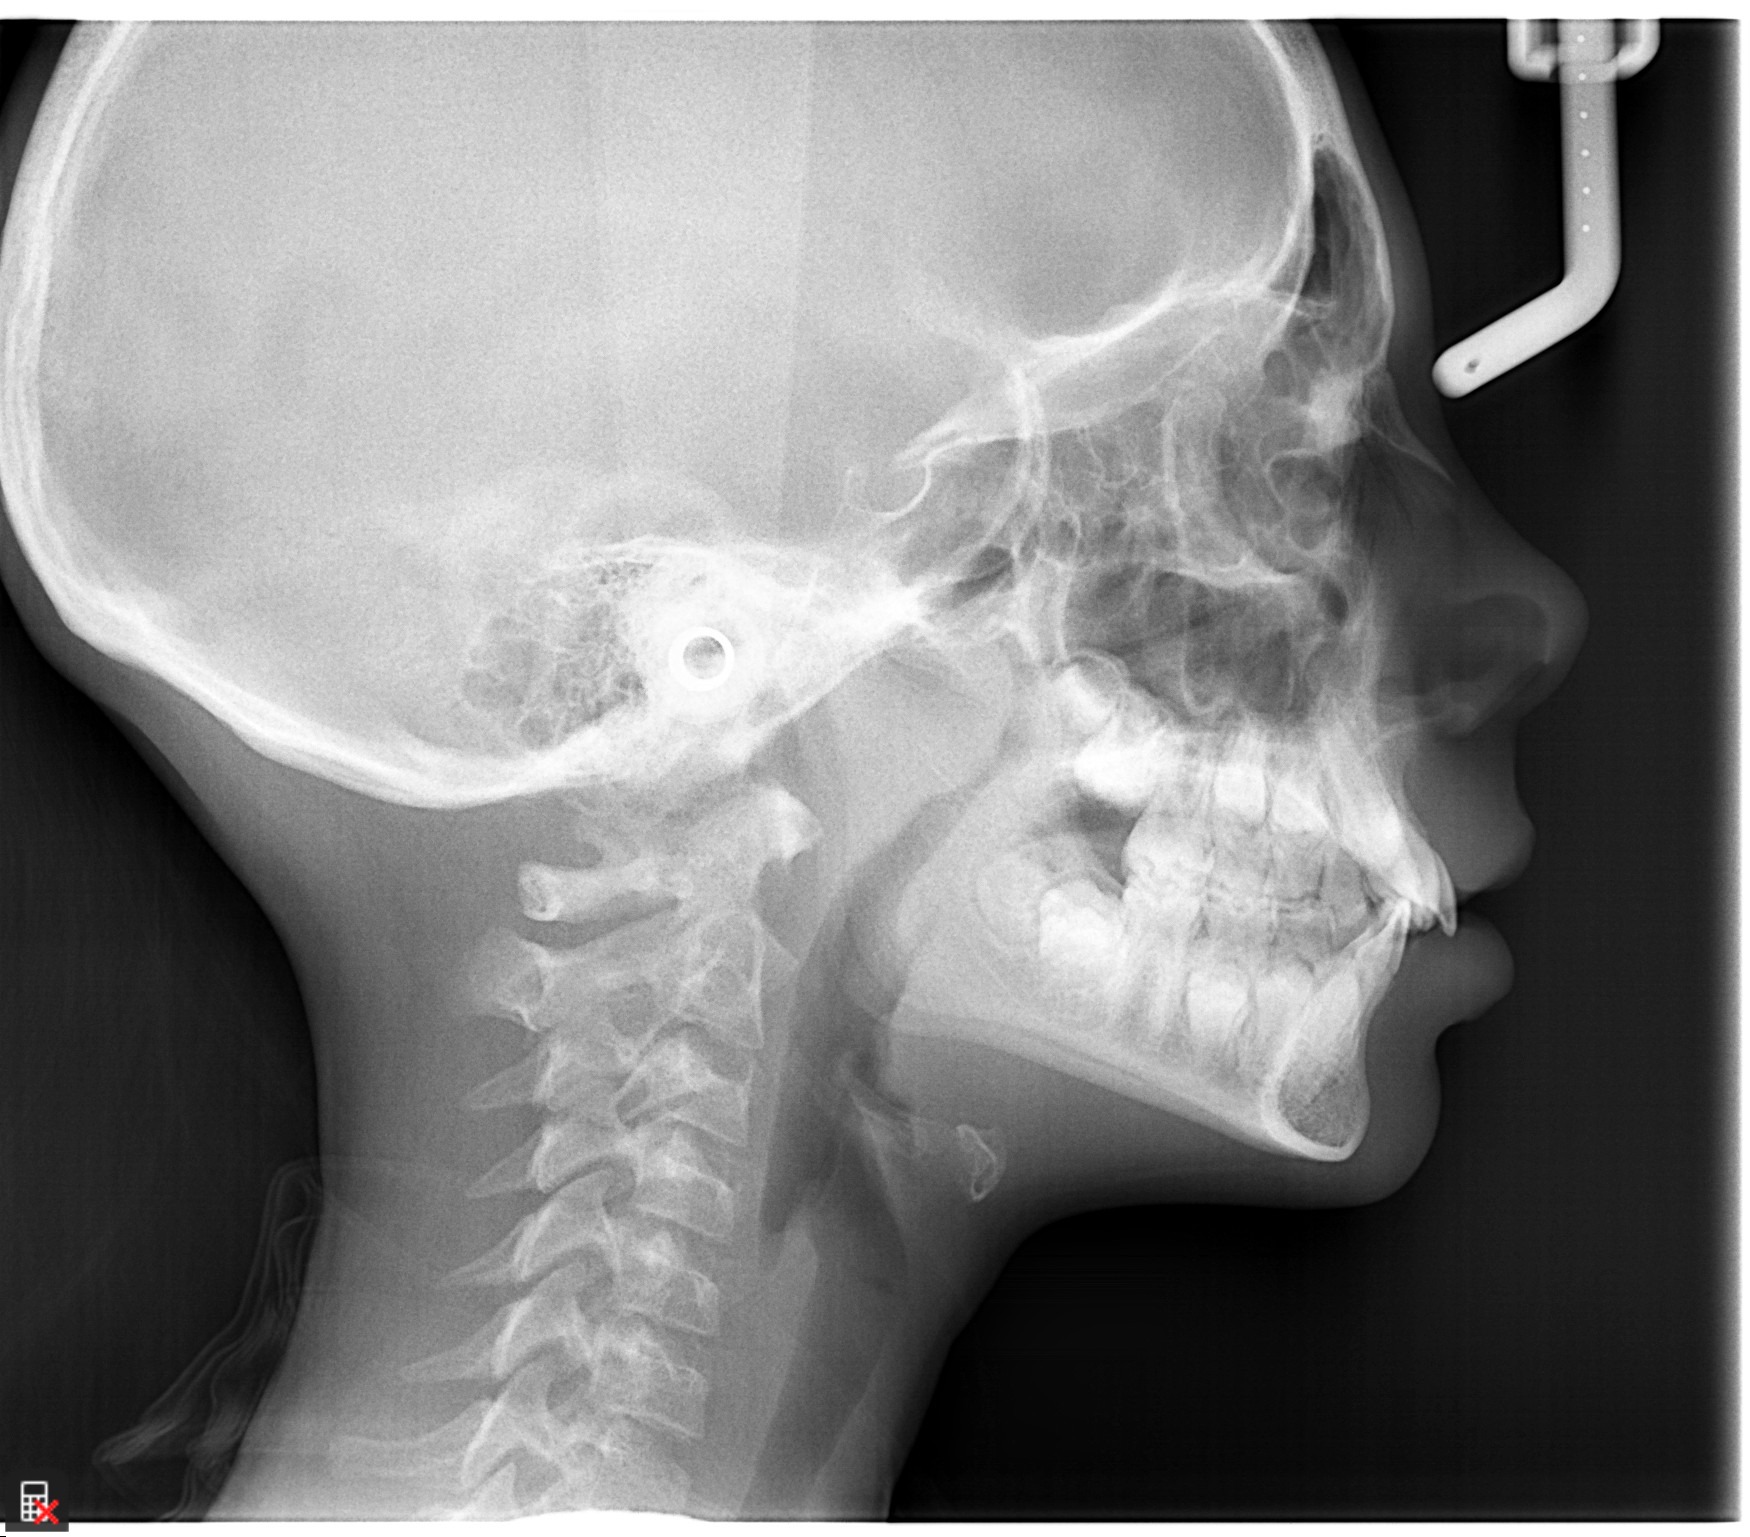

This is a 9yo girl with a high esthetic desire (wants to be a model/actor). She avulsed tooth #9 about 3 years ago, and she has been under treatment with other endodontists. I guess they attempted revascularization with MTA about year ago. #9 is ankylotic with a few mm’s infraposition. It is gray due to the MTA. #8 is slightly yellow/white due to calcification/obliteration but she says she feels cold testing and it is otherwise asymptomatic.